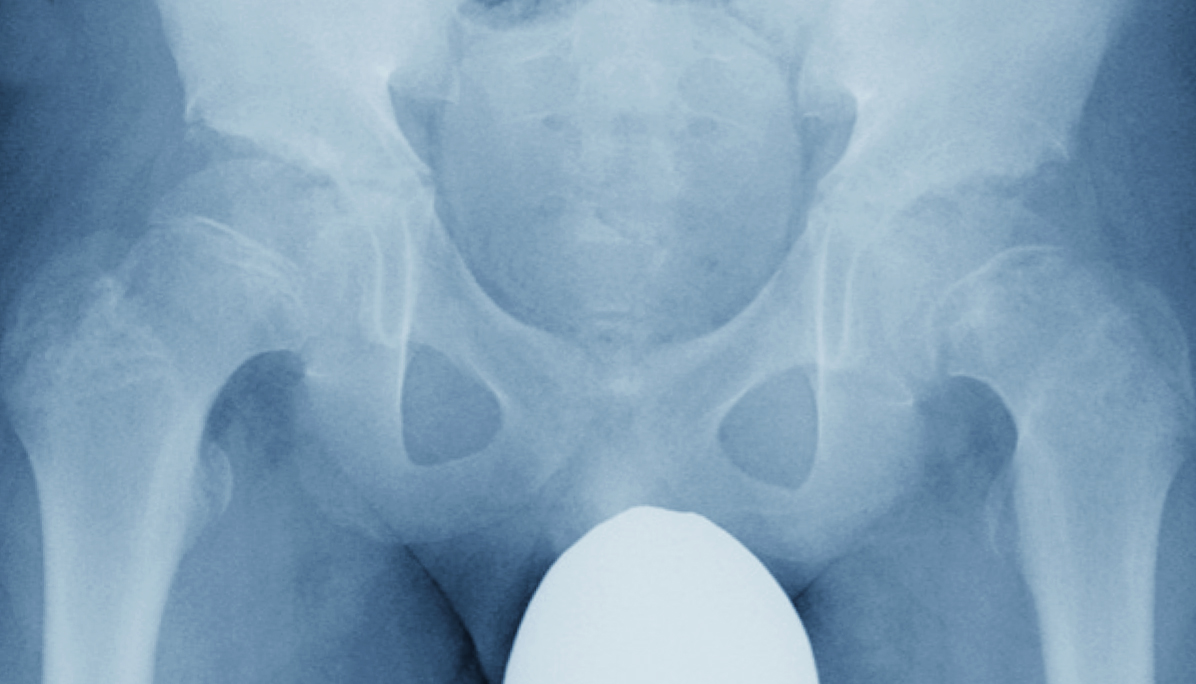

股関節の一般的な検査

疾患の治療を行う前に、原因を明らかにしなければ治療は難しいです。

診察での検査に加えて、MRIやCTを用いる「画像検査」を行うことで骨の状態などを調べ、何が原因かを探ったのち、適切な治療を行っていきます。